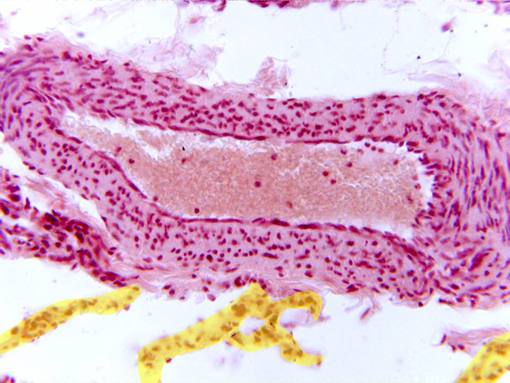

Detail of a small pulmonary venule observed with the

objective of 40x. The layers that integrate the wall are the

following:

intima

(formed by endothelium in contact with the lumen of the

venule),

media

(showing the nuclei of the conjunctive cells), and part of

the

adventitia

(more externally located).

Around the vessel are visible some interalveolar septa

(yellow).